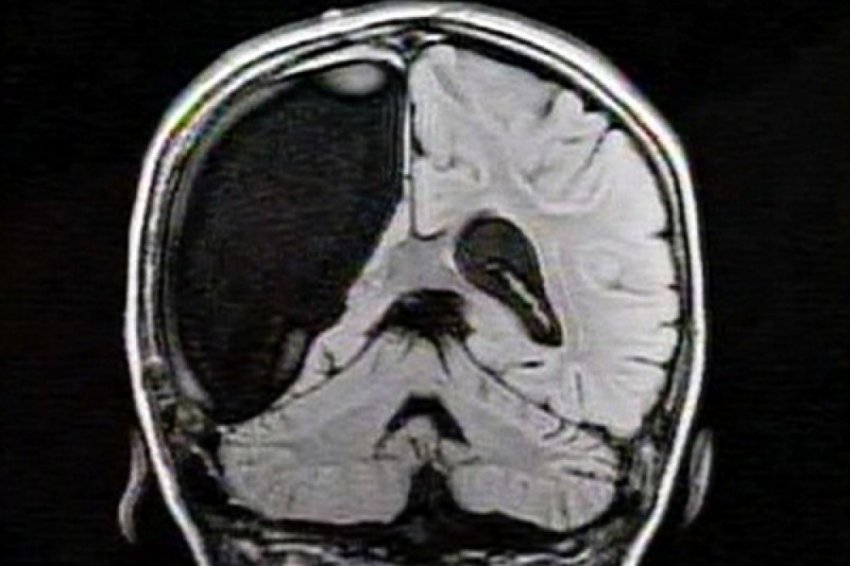

Медицина идет вперед семимильными шагами, изучаются все органы и их взаимодействие, изобретаются методы лечения тяжелых болезней, новые лекарства и приборы. Однако, головной мозг, как и прежде, остается самой большой загадкой для врачей. Мозг управляет всей работой нервной системы человека, его влияние на функции всех органов постоянно изучаются, данные дополняются, методики лечения совершенствуются.

Здоровье мозга является приоритетной темой изучения медиков всех стран. Неврологи придают огромное значение обмену актуальной информацией в этой области исследований, в привлечении государственной помощи к проведению изысканий и клинических испытаний. Всячески приветствуются новые технологии, которые приходят на помощь докторам в процессе диагностики и лечения заболеваний мозга.